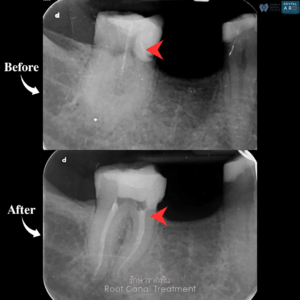

รักษารากฟัน

คือ การรักษาฟันที่เกิดการอักเสบและติดเชื้อภายในโพรงประสาทฟัน และเนื้อเยื่อรอบปลายรากฟัน อันมีสาเหตุมาการอักเสบและติดเชื้อภายในรากฟัน โดยทันตแพทย์จะทำการทำความสะอาดและใส่ยาในคลองรากฟัน และทำการอุดรากฟันเป็นขั้นตอนสุดท้าย การรักษารากฟันจะช่วยเก็บรักษาฟันให้สามารถคงอยู่ในช่องปากต่อได้ โดยไม่ต้องถอนฟันและไม่ต้องใส่ฟันทดแทน